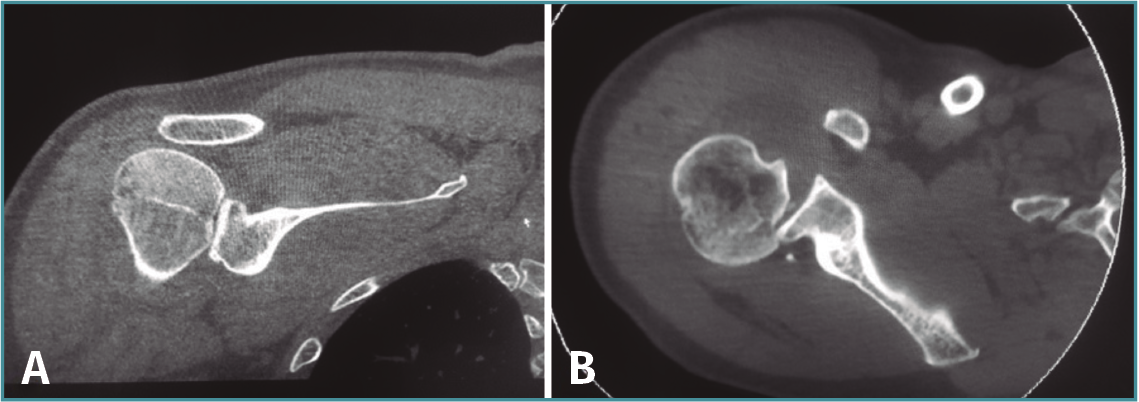

Ante esta situación, se solicita una tomografía computarizada (TC) para comprobar las lesiones asociadas. En esta se muestra una persistencia de la luxación posterior, asociada a una lesión de Hill-Sachs y de Bankart invertidas (Figura 2).

Figura 2. Cortes coronal (A) y axial (B) de la tomografía computarizada en los que se observan las lesiones de Hill-Sachs y Bankart invertidas.